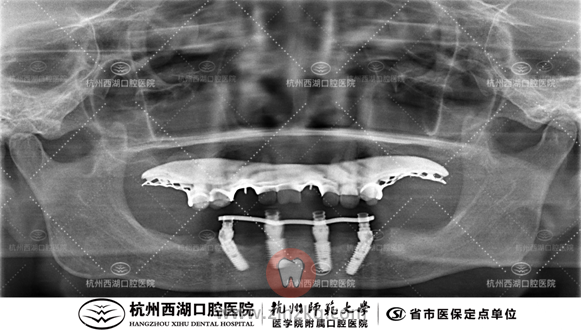

术前CBCT照如下